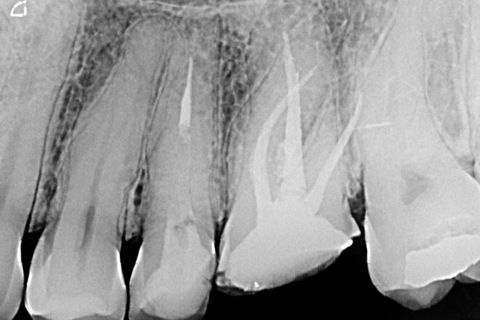

Radiografia de controle de 13 meses evidenciando normalidade dos tecidos perirradiculares com restauração final em posição.